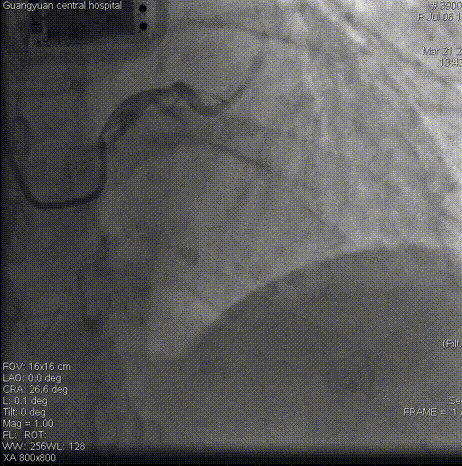

术毕影像

PCI术后结果及随访

即刻结果:提高手术安全性,提高手术效率。该款导引延长导管在此次使用过程中未发生器械不良事件。